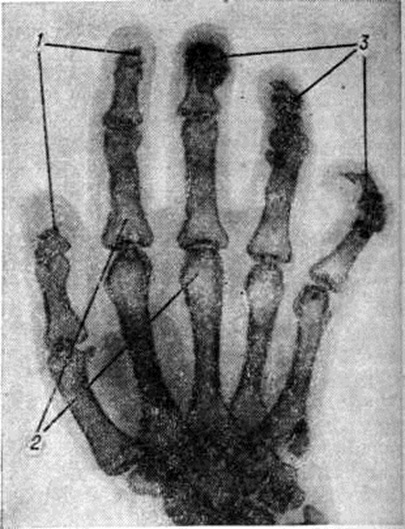

Типичными для системной Склеродермия изменениями со стороны мягких тканей, костей и суставов (рисунок 4) являются участки кальциноза (смотри полный свод знаний) в подкожной клетчатке, преимущественно концевых отделов пальцев рук, реже — стоп, области локтевых, коленных и других суставов. Остеолиз (смотри полный свод знаний) наблюдается в ногтевых фалангах пальцев рук, стоп, венечных отростках ветвей нижней челюсти, дистальных отделах лучевой и локтевой костей, задних отделах рёбер и некоторых других костях. Отмечаются околосуставной остеопороз (смотри полный свод знаний), сужение суставных щелей, иногда единичные эрозии на поверхности суставного хряща и костные анкилозы (смотри полный свод знаний), чаще в суставах запястья.